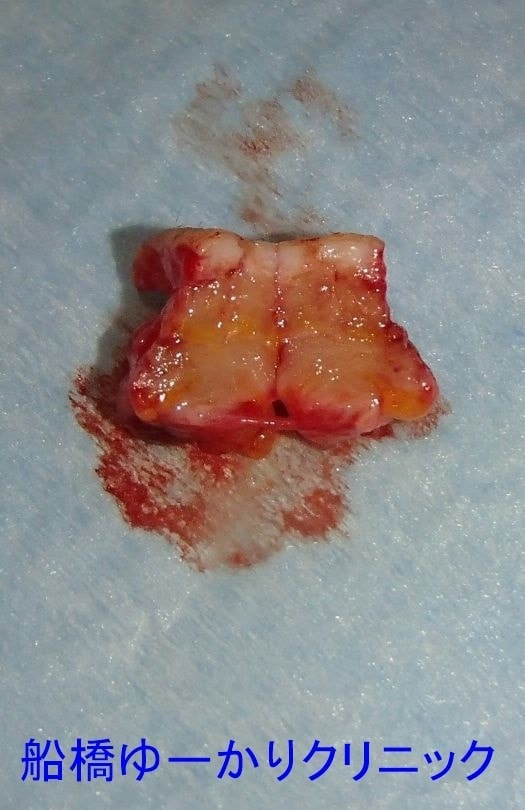

摘出組織

右こめかみのしこり。生まれつきで、徐々に増大。摘出組織には毛髪が含まれていました。

術後の圧迫は24時間、その後の出血は少量。自宅で自己処置を行い、1週間後に抜糸